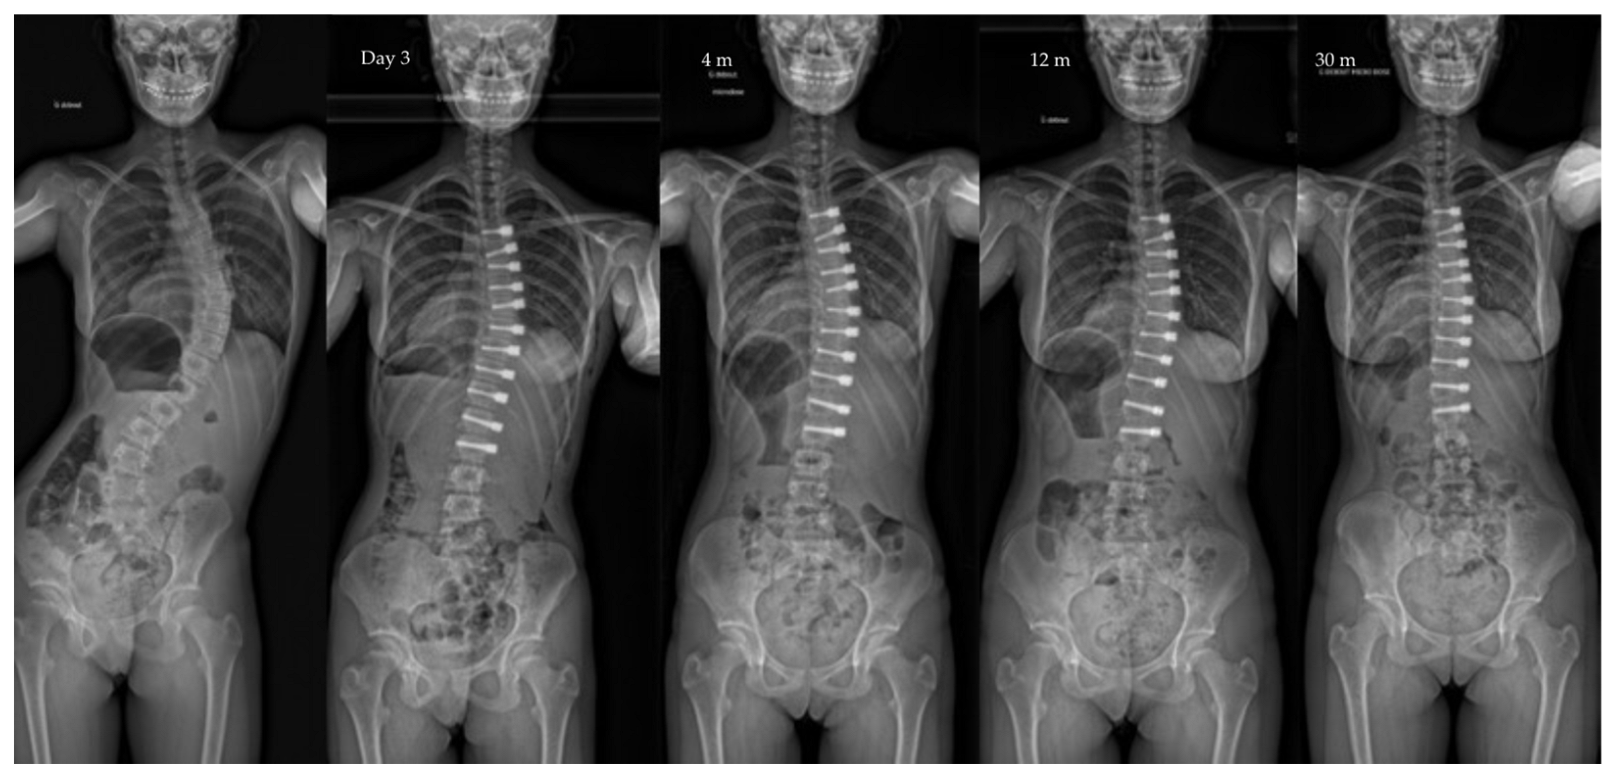

| Major curve | 49°(8,9°) | 27°(12°) | 22°(12°) | 19°(14°) | <0.01 |

| Secondary curve | 27°(14°) | 23°(15°) | 22°(11°) | 17°(10°) | <0.01 |

| Instrumented curve | NA | 26°(11°) | 23°(10°) | 20°(14°) | <0.01 |